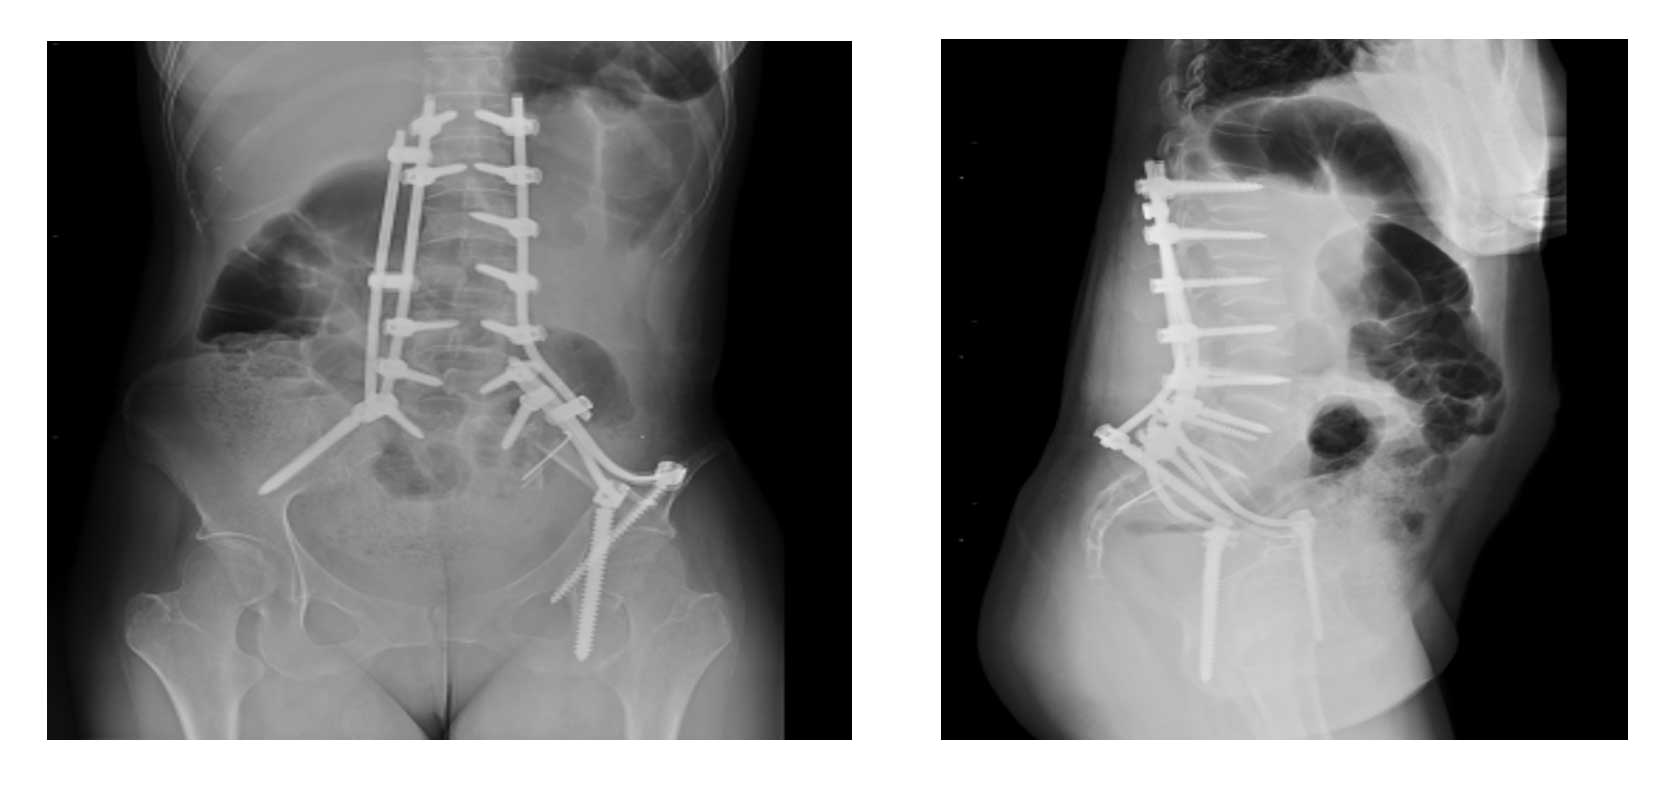

Ameliyat Sonrası: Röntgende parsiyel laminektomi+korpektomi sonrası yapılan çimentolama ve lumbopelvik fiksasyon görülmekte